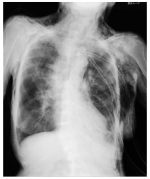

On November 18, the quiz focuses on systolic heart murmurs. First, you will identify the point of maximal intensity of the murmur. Then, you will divide systole into three phases—early, mid, and late—and determine in which phase the murmur is heard. (November 18, 2025)